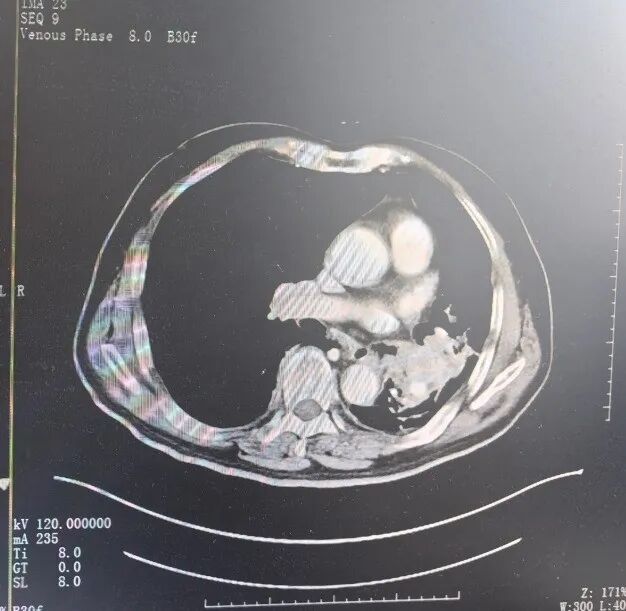

△入院时CT影像图